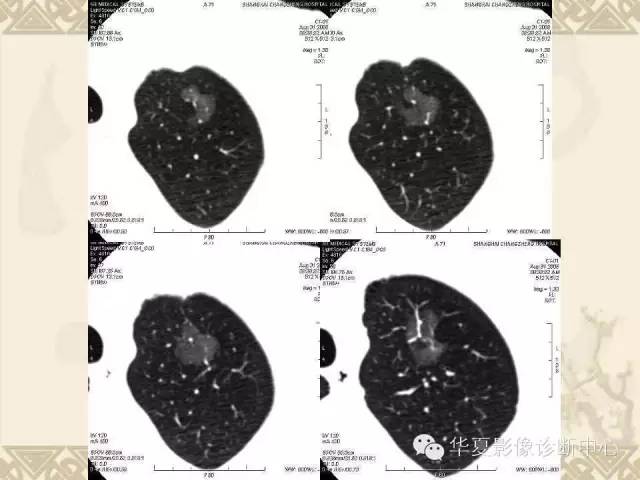

肺内磨玻璃样结节的影像诊断与处理对策